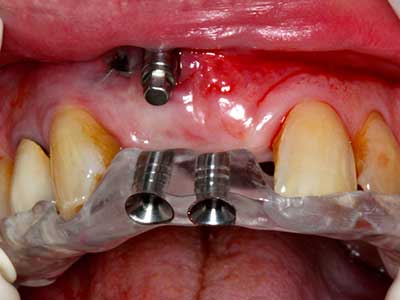

Indication: Preparation near nerves

When surgical procedures are performed on bone in the immediate vicinity of sensitive structures such as blood vessels or nerves, rotary instruments pose a significant risk of iatrogenic injury. Piezoelectric devices can be helpful for preparation of bone covers and removal of hard tissue close to nerves, particularly for exposure of nerves after iatrogenic injury but also during nerve lateralization for resective and reconstructive procedures or implant placement (Fig. 17-20). Light contact between the piezotip and the nerve does not generally result in damage but proceeding incautiously with saw-like motions or attachments where a residual bone substrate remains may cause temporary or even permanent nerve damage. However, the risk of damage is considered to be substantially lower than when using saws or milling instruments (Pereira, Gealh et al. 2014).